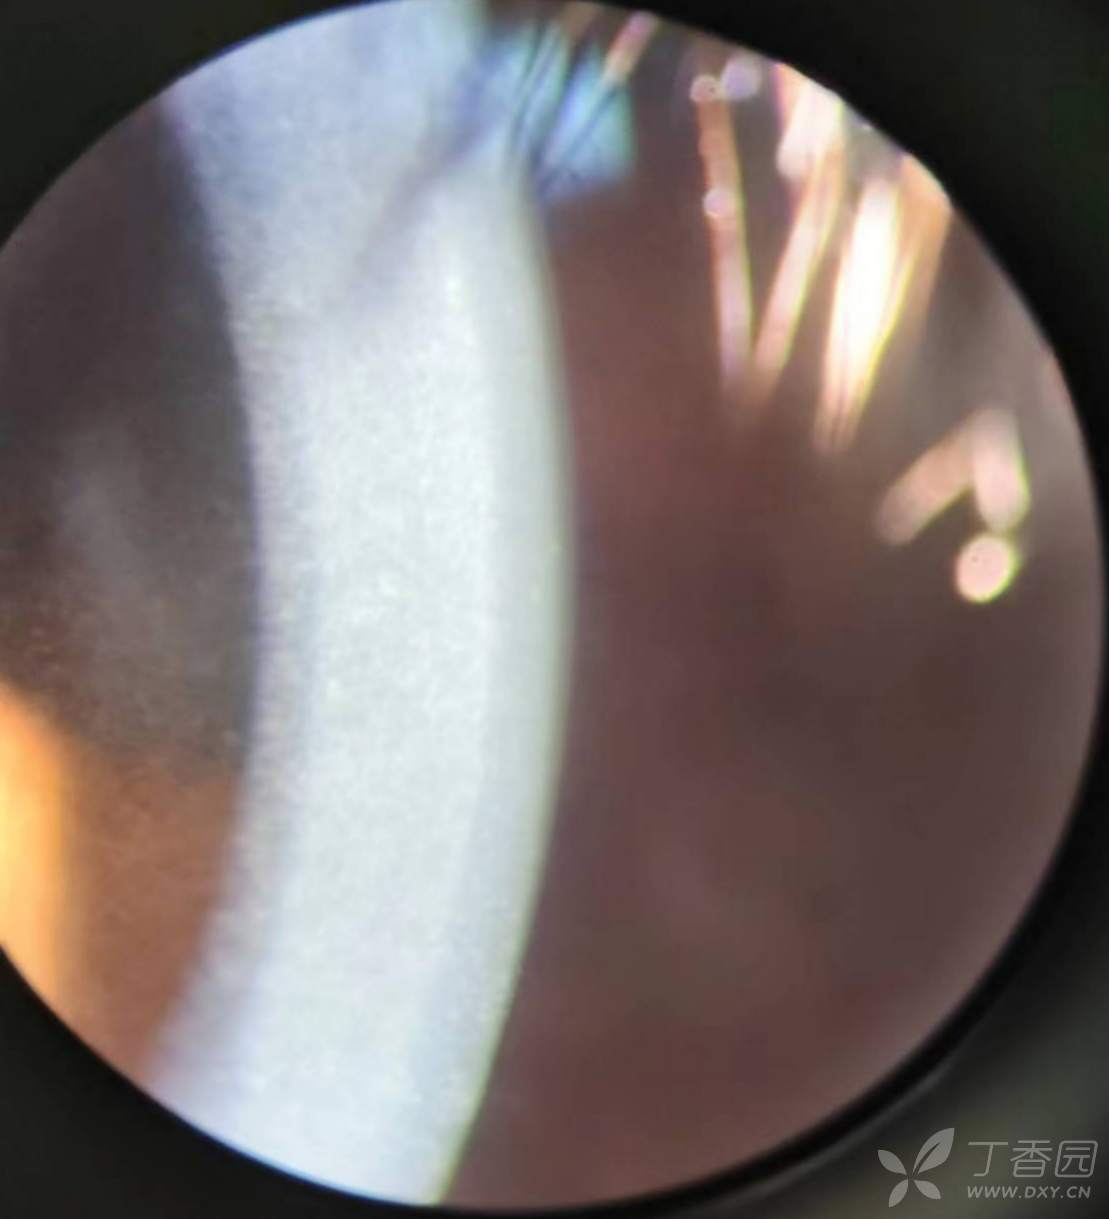

患者男性30岁,因为左眼红痛三天就诊,在中日友好医院诊断左泡性角膜炎,给予左眼典必殊滴眼液治疗。次日我院复查。既往曾发现双眼角膜混浊。检查时右眼前节无活动性炎症,左眼睫状充血并颞下和鼻侧周边浅层角膜灰白泡性浸润结节病变(符合泡性角膜炎),这不是今天讨论的重点。要讨论的是患者双眼都有一特征性改变:双眼角膜广泛后弹力层附近深基质大量细小灰尘状细小颗粒混浊,中部和浅层基质相对清亮,双眼角膜上皮点状脱落轻度糜烂。右眼并无充血或浸润。双眼前房是正常的。

以上是患者右眼角膜的裂隙灯照片。左眼在此相同病理改变基础上还同时患有泡性角膜炎(未予照相记录)。